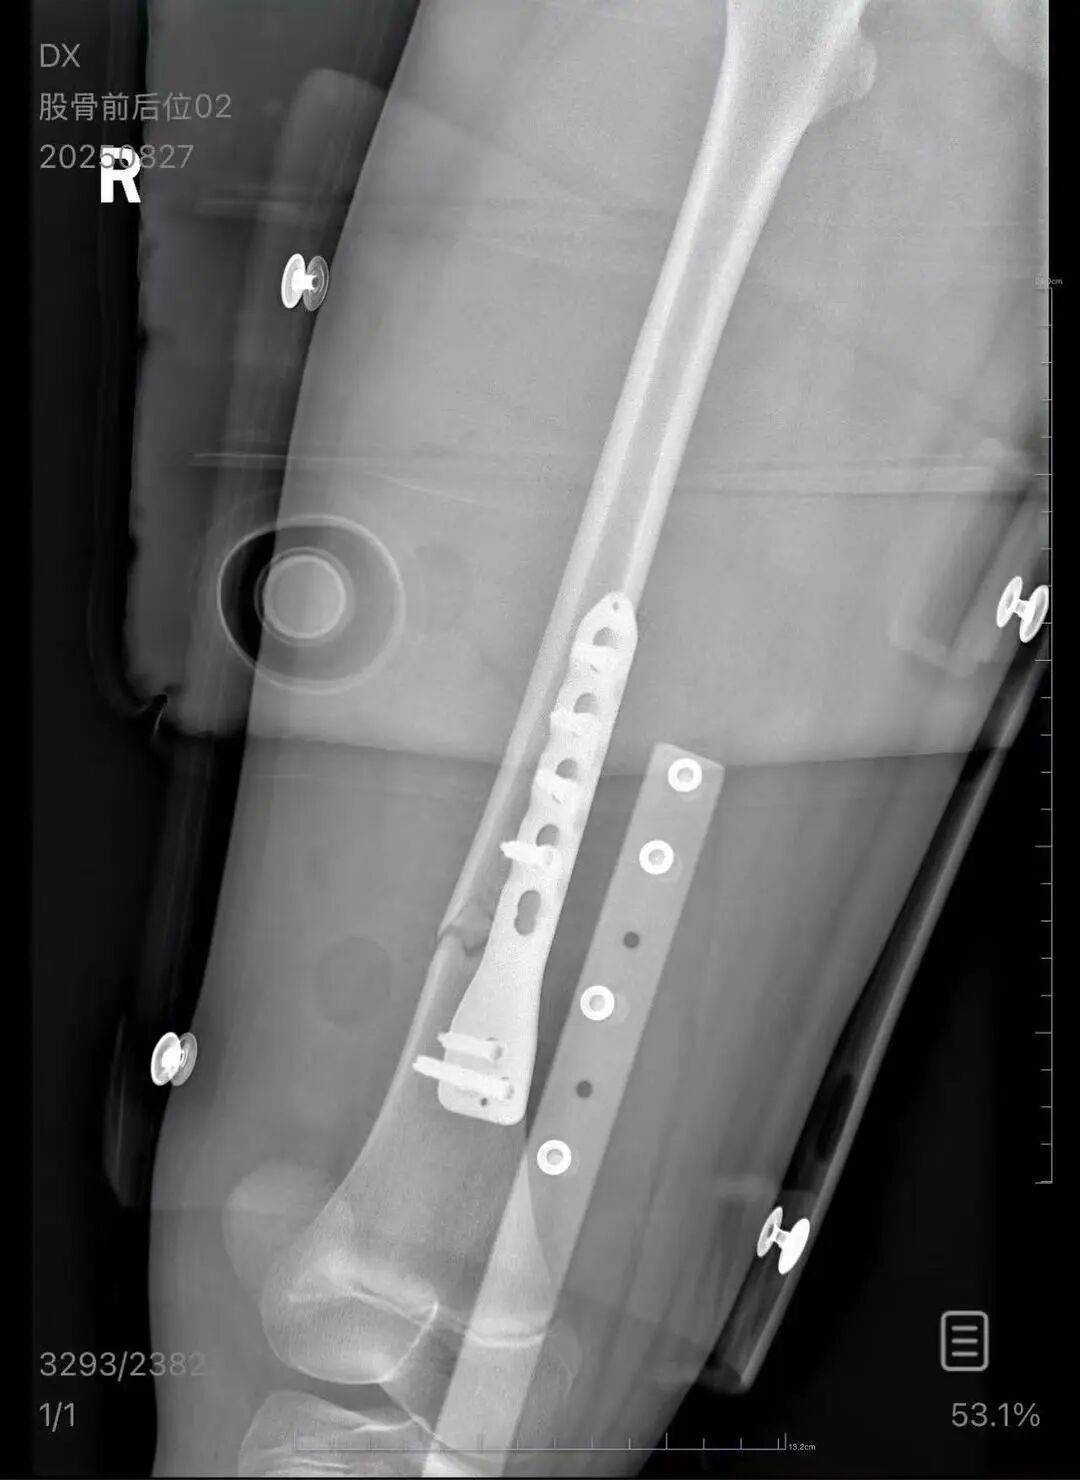

▲朱女士女儿手术后拍的X光片 受访者供图

朱女士向记者出示的医院病历显示,8月24日凌晨,朱女士的女儿到医院就诊。医院诊断朱女士的女儿右股骨骨折,需要住院进一步治疗。

朱女士出示的报警回执显示,8月24日凌晨2点22分,上海铁路公安处无锡站派出所接到报案。报案人称,在某列车上,快要到无锡站时,上铺的乘客下床时没抓稳,导致孩子大腿骨折。